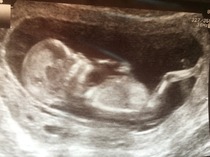

Here's some pics!

August 2016 (3) - scans fast approaching, teeny tiny bumps appearing, and sickness easing....we hope!

MrsZumba and Silver - gorgeous scan pics! Hope you're basking in the relief and excitement now - such a lovely feeling. Owlina did you have your scan too?